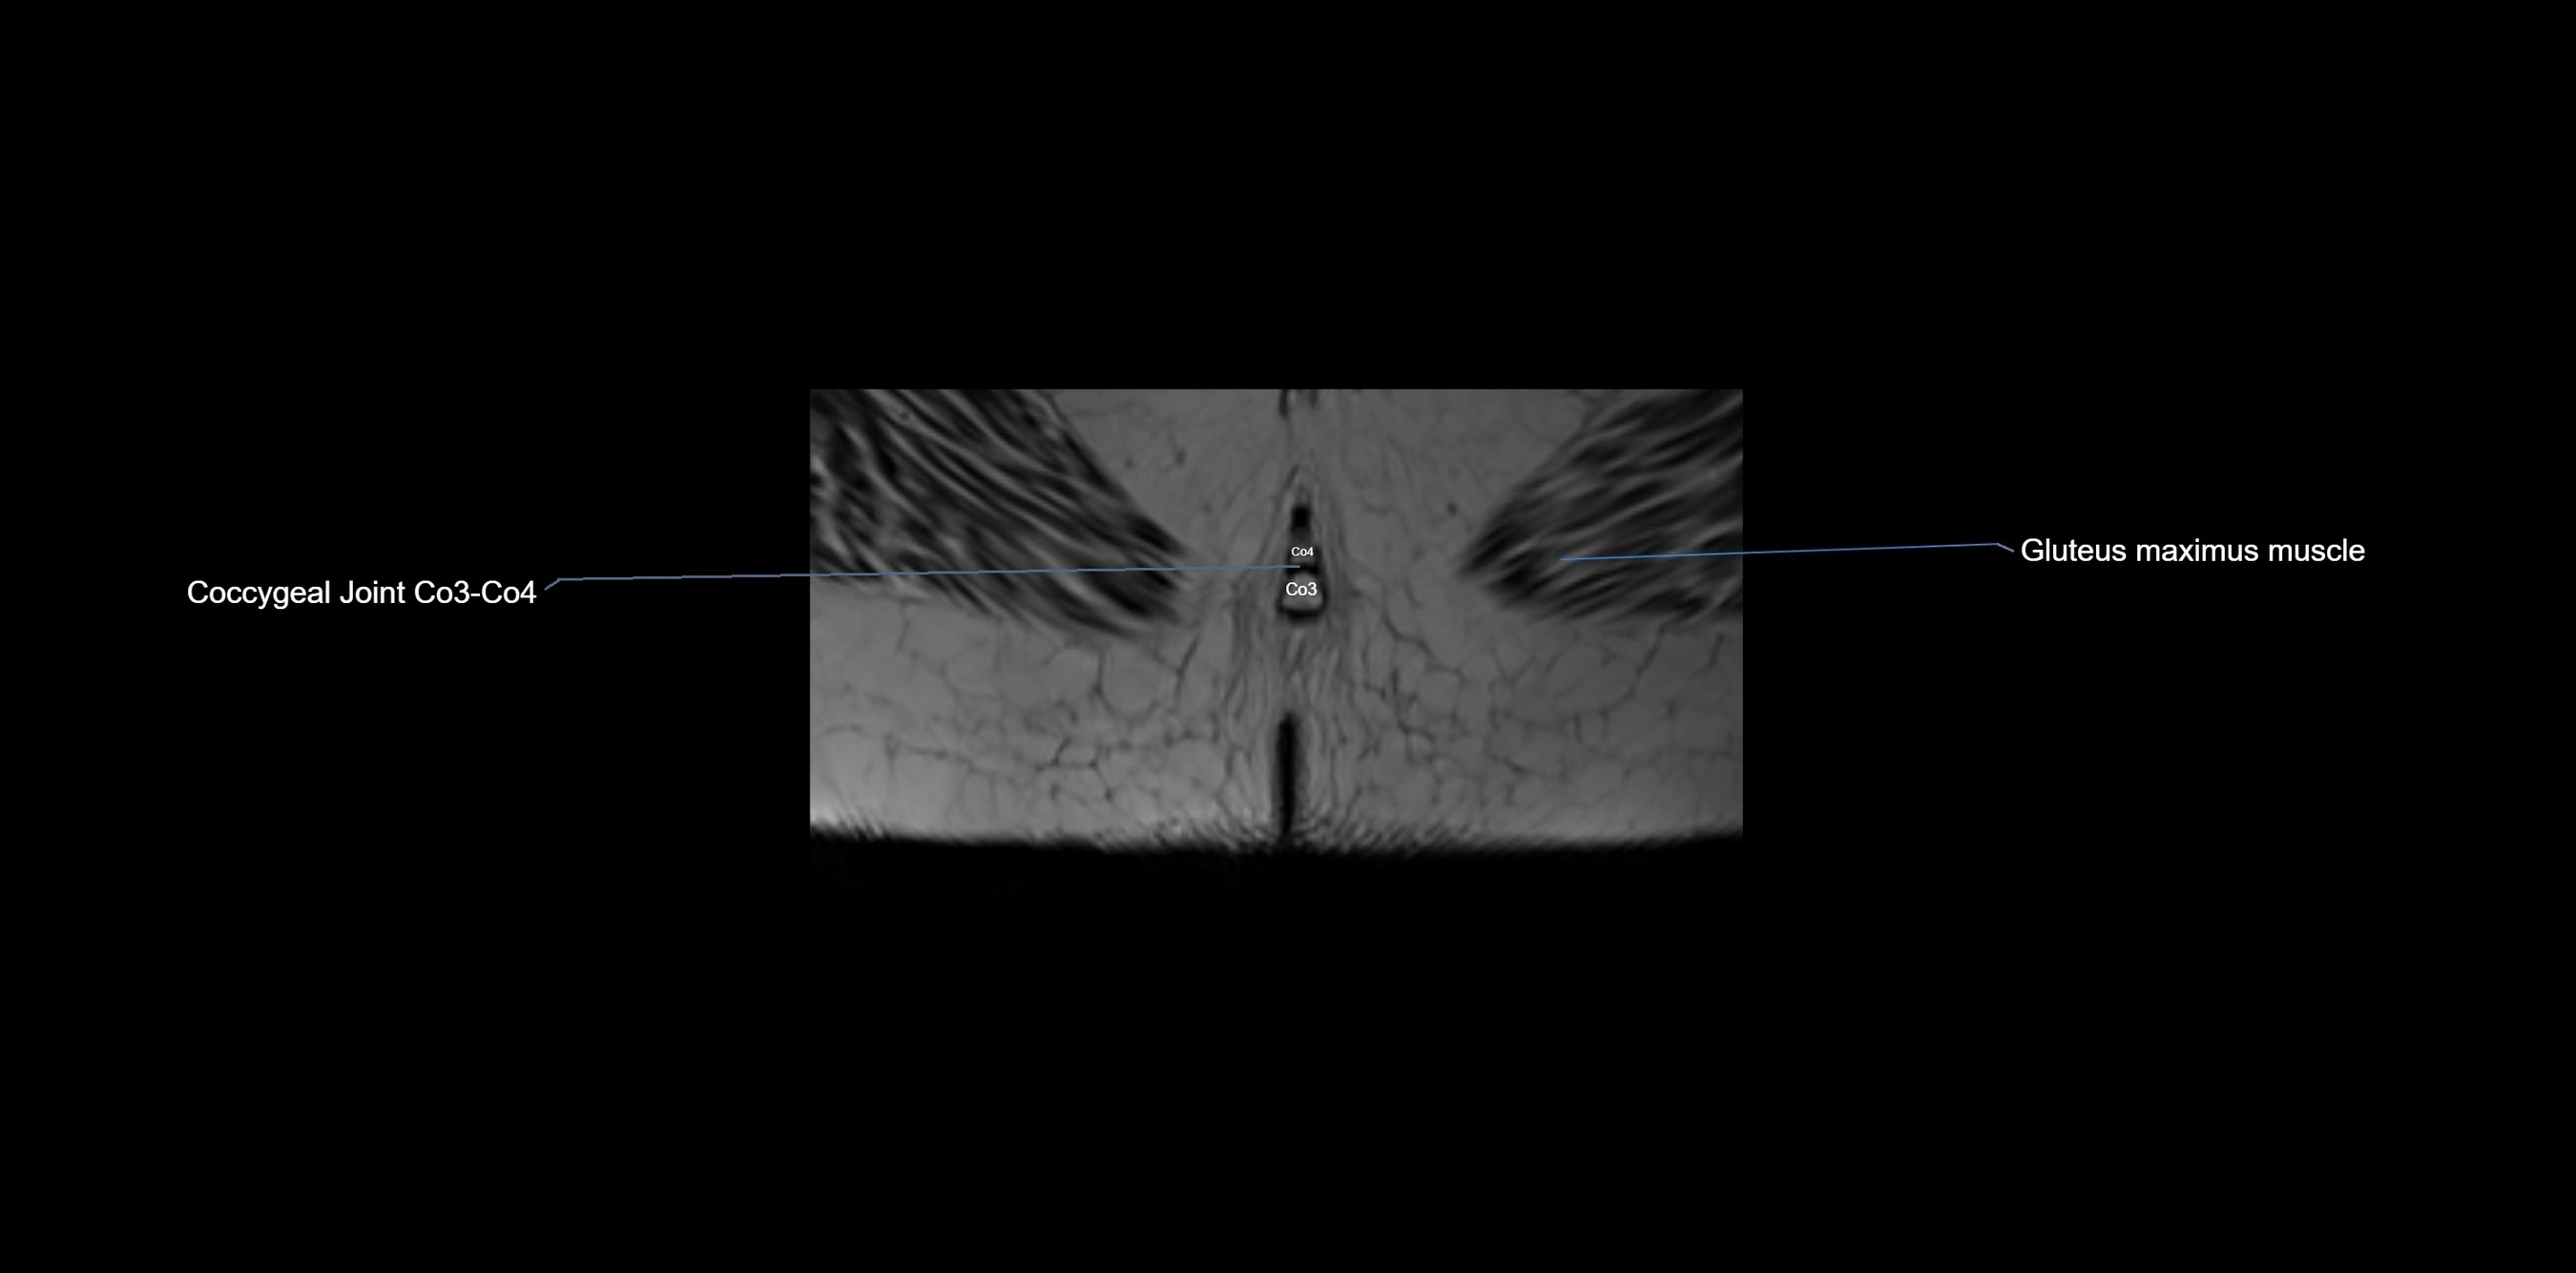

MRI image

image

MRI Appearance

T1-weighted images:

• Cortical bone appears very low signal (dark); marrow shows intermediate signal

• Iliac fossa fat is bright against low-signal cortex

T2-weighted images:

• Cortical bone remains dark

• Marrow signal varies depending on fat content; edema or tumor shows hyperintensity

STIR:

• Suppresses fat, making bone marrow edema, fractures, or infiltrative lesions appear bright

• Excellent for trauma, sacroiliitis, and metastatic evaluation